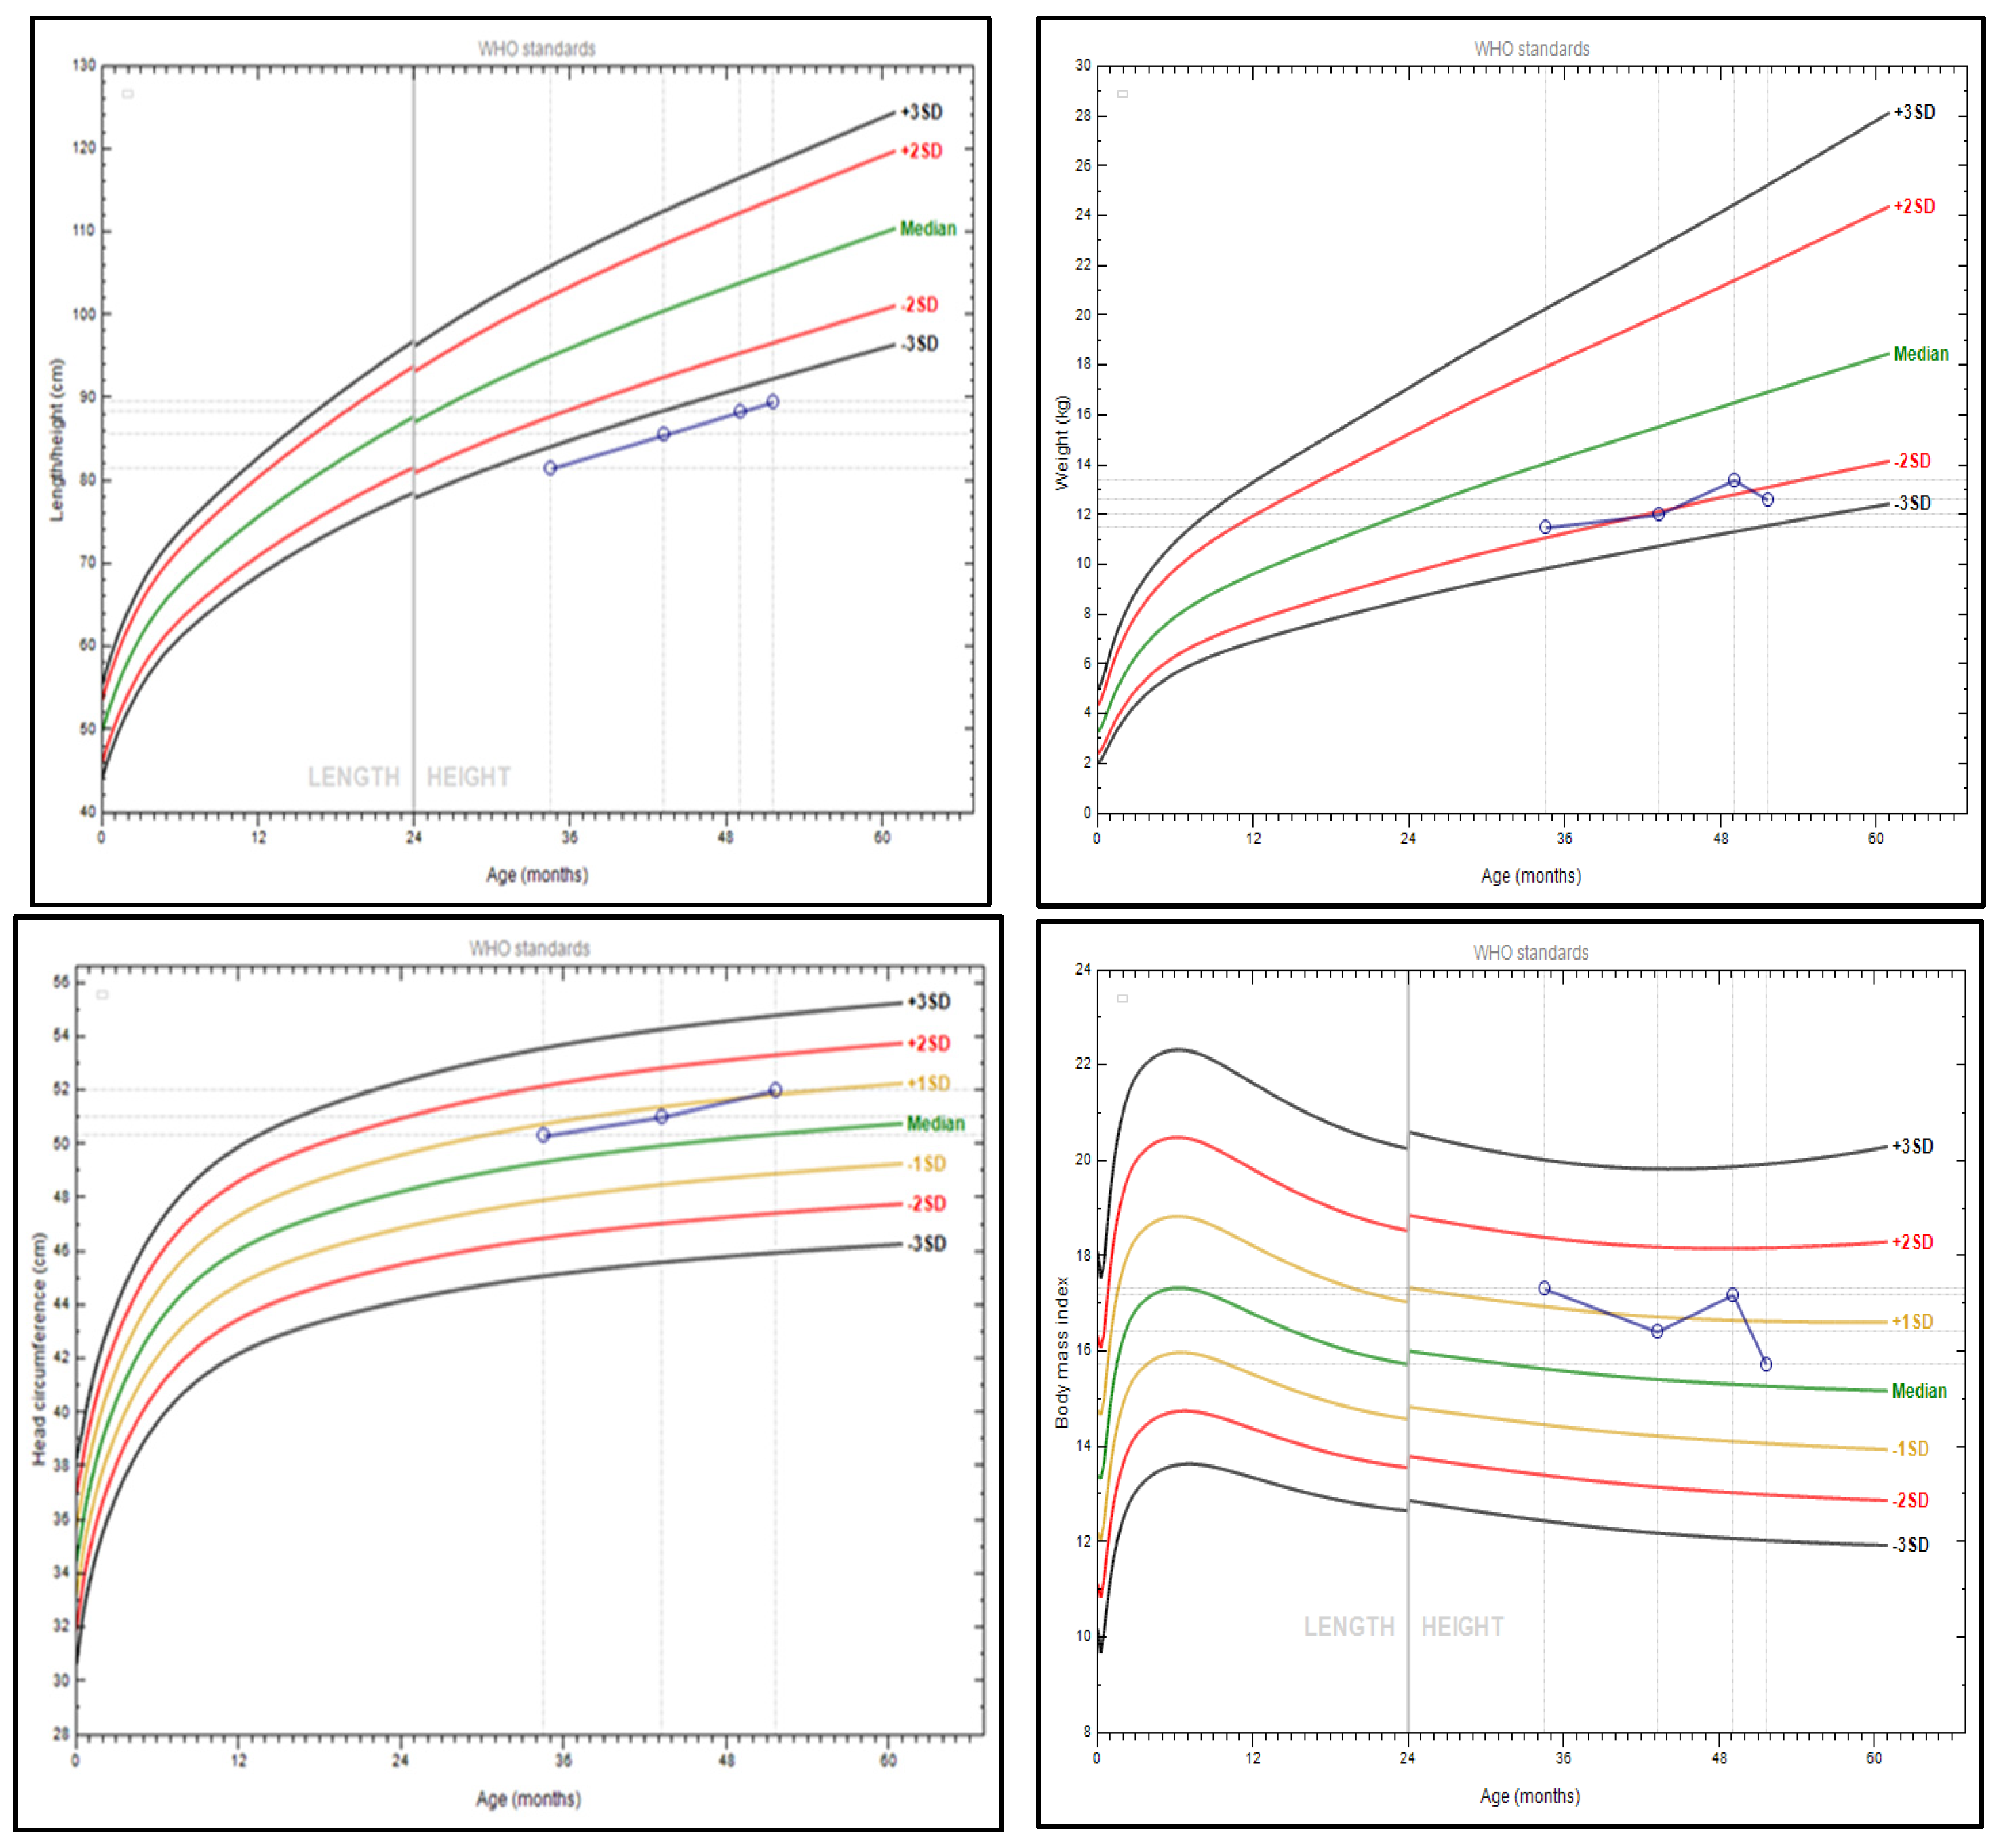

3.1. Patient’s Phenotype

3.3. Follow-Up